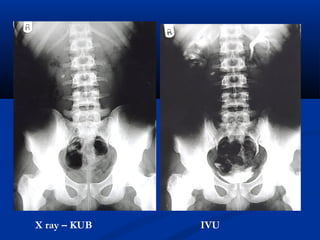

X ray – KUB   IVU

Double J stent